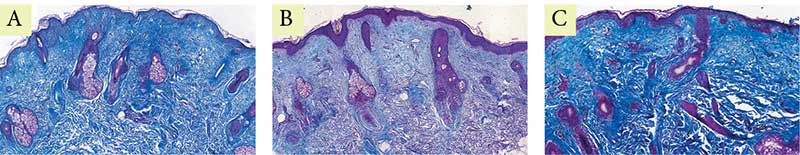

Рис. 3. Пациентка Л. Окраска по Массону: A – до процедуры; B – через месяц после процедуры; C – через пять месяцев после процедуры

В гистологических исследованиях эпидермиса через месяц отмечается уменьшение гиперкератоза, сглаживание эпидермальных гребней. В дерме отмечены выраженные лимфоцитарные инфильтраты, что свидетельствует о незавершенном воспалительном процессе, а также единичные участки с увеличенным количеством упорядоченных коллагеновых волокон, что подтверждает начало и продолжение синтеза коллагена и его реорганизации. Через пять месяцев отмечается выраженное увеличение количества и упорядочение коллагеновых и эластиновых волокон. Значительное утолщение сосочкового и сетчатого слоев дермы. Признаков фиброза отмечено не было (рис. 1–3).  До проведения процедуры экспрессия коллагена I типа в дерме была выражена слабо и неравномерно. Волокна преимущественно локализовались в сетчатом слое, имели разобщенный характер, с признаками дезорганизации и выраженными участками разрыхления межволоконного матрикса; в сосочковом слое экспрессия была минимальна (рис. 4А). Через месяц после процедуры отмечается умеренное усиление иммуногистохимической экспрессии коллагена I типа в верхних отделах сетчатого слоя дермы. Волокна становятся более четко очерченными и упорядоченными, формируется более компактная волокнистая структура, однако выраженного диффузного увеличения интенсивности окрашивания не наблюдается (рис. 4B). Через пять месяцев сохраняется тенденция к структурной организации дермального матрикса без существенного дополнительного нарастания экспрессии коллагена I типа. Коллагеновые волокна располагаются более равномерно и компактно, что свидетельствует о стабилизации ремоделирования дермы без признаков избыточного фибротического ответа (рис. 4C).